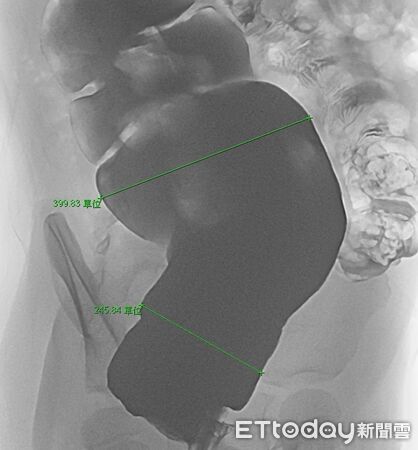

▲「巨結腸症」之影像特徵。

經過張經旼醫師詳細詢問病史,並安排一系列檢查,包括影像學與腸道評估,最終女童確診為先天性的「巨結腸症」。醫師說明,巨結腸症是因腸道神經發育異常,導致腸道蠕動不足,糞便無法順利排出,症狀常被誤以為只是單純便秘,因而延誤診斷。